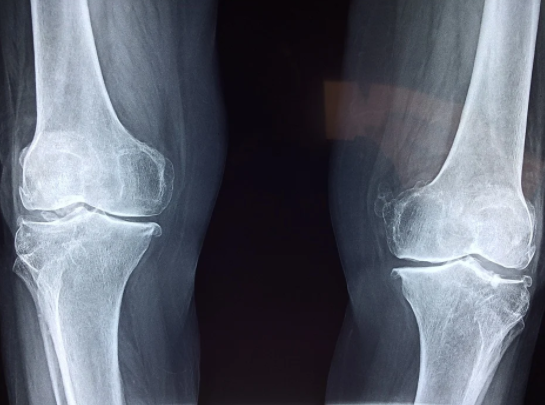

날씨가 갑자기 추워지면 무릎이 시린 증상이 더욱 심해질 가능성도 있으며 여름에 냉방이 심할 때 무릎이 시큰거려서 고생할 가능성도 있다. 하지만 가장 흔하게 무릎이 시린 증상을 겪는 사람들은 고령자일 것이다. 무릎 관절이 시린 이유 중 하나로 꼽히는 퇴행성 관절염과 같은 이유로 기온이 떨어졌을 때 증상이 더욱 심해질 수 있다.

퇴행성 관절염의 증상은 사람마다 매우 다양하다. 무릎이 저리고 시린 경우, 낮에는 통증이 덜하다가도 밤이 되면 통증이 심해지는 경우, 아침에 일어날 때 아픈 경우, 산에서 내려올 때 아픈 경우, 계단 내려갈 때 무릎이 불편한 경우, 무릎이 시큰거리는 경우, 무릎이 아파서 일상생활을 하는데 있어서 문제가 생기는 경우 이 때는 이미 관절염이 생긴 것이라 생각해볼 수 있다.

나이가 들면 무릎관절과 인대, 근육 등이 자연스럽게 약해지면서 염증이 생길 가능성이 있다. 염증이 생기면 해당 부위에는 열이 나기 때문에 똑같은 기온에 노출되더라도 유독 무릎이 시린 증상이 나타날 수 있다. 더군다나 관절은 외부의 온도변화에 예민하기 때문에 퇴행성 관절염을 겪는 사람은 날씨가 따뜻한 날에도 에어컨 바람이 무릎에 닿으면 무릎 관절의 주변과 인대의 경직으로 인해서 무릎이 시큰거라거나 아파서 불편함을 느낄 가능성도 있다.

퇴행성 관절염은 무릎이 시린 이유 중 하나이지만, 무릎 뿐만 아니라 신체의 관절이 존재하는 부위라면 어디든 생길 수 있는 질병 중 하나이다. 손가락이나 어깨, 허리, 발목 등 신체의 여러 관절부위에도 나타날 수 있는 증상이다.

하지만 관절에 많은 사람들이 불편함을 호소하는 이유는 무릎관절이 몸의 하중을 받아내는 관절이기 때문일 것이다.

퇴행성관절염은 40대~50대에 노화와 함께 나타나며, 무릎이 시큰거리거나 무릎이 아파서 불편한 경우에는 퇴행성 관절염의 초기증상을 의심해보아야 한다.